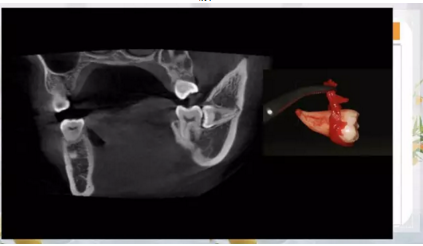

27.png

28.png